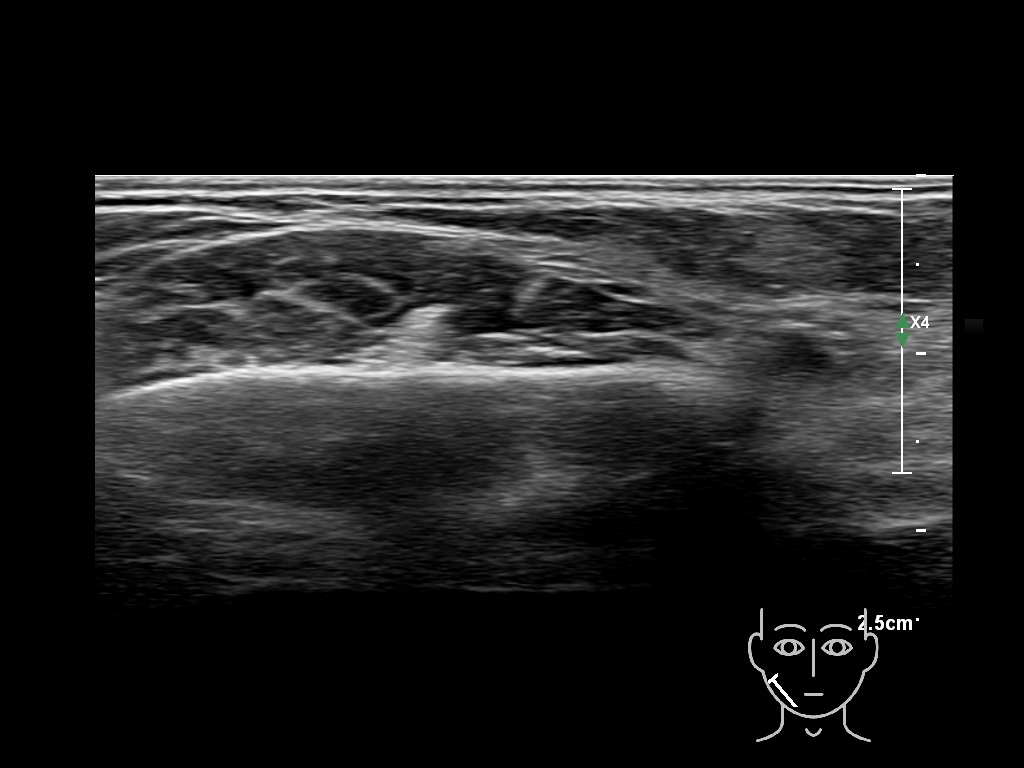

Draw in the image on the right where the fillers are located. To check if your answer is correct, please click on the secondary image.

Draw in the second image below where the fillers are located. To check if your answer is correct, swipe the first image to the right.